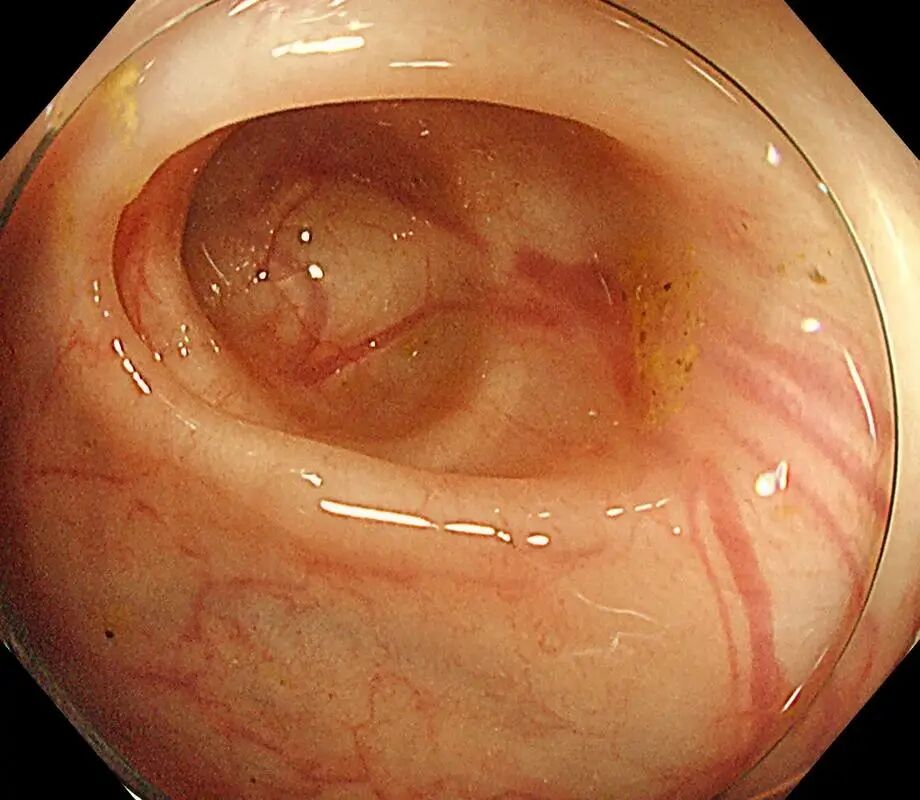

2、结肠镜:

伸个“摄像头软管”进肠道,

直接看小口袋(顺便还能切息肉)。